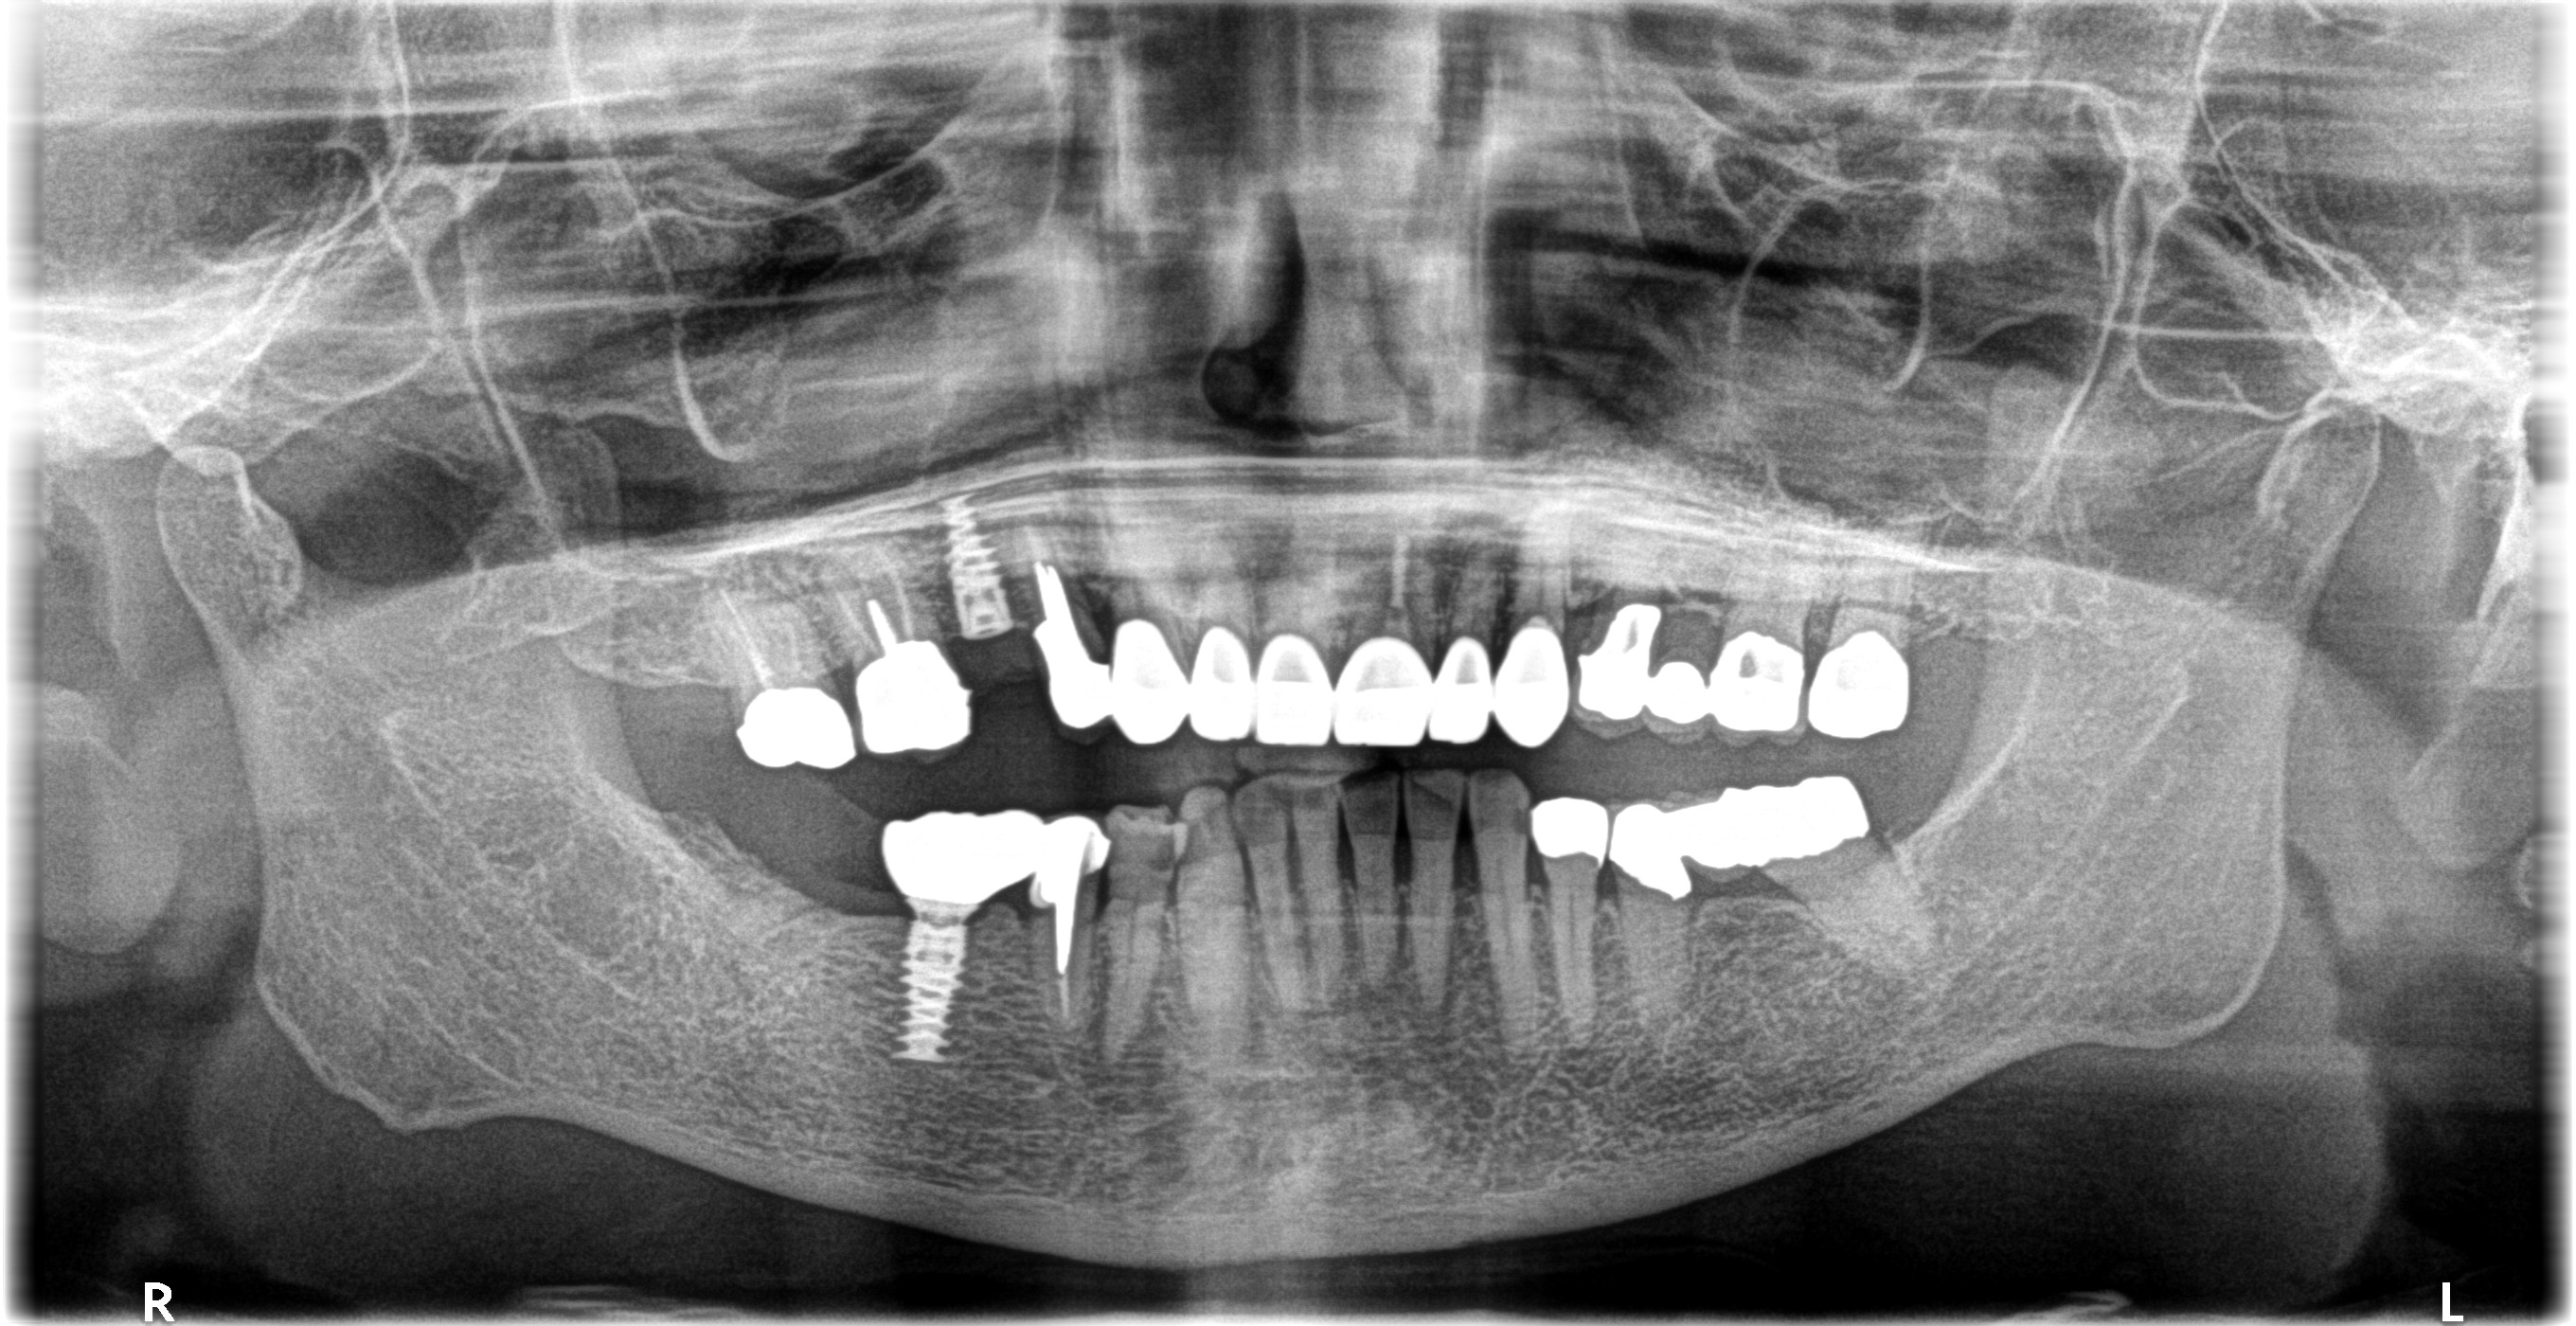

こちらがレントゲンになります

もともと右上にBr.が入っていて手前の第一小臼歯に破折がありました

しばらく様子をみていたのですが、骨吸収が進んでいたので処置を開始することとなりました

まずはポンティックを除去しImplantを埋入➡︎インテグレーション(骨と結合すること)を確認後、型取りをして仮歯を用意➡︎抜歯・GBRの順で処置を行いました

抜いた場所にはImplantは入れずカンチレバー式の上部構造を入れる予定です

◎カンチレバー式とは、1つの片側支台歯で支えられている固定性補綴装置のこと

🦷治療内容:Implant(Nobel Biocare)・GBR・IVS・フルジルコニア(ポンティック)